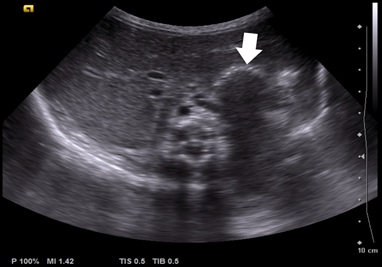

However, on day seven, frequent episodes of tachypnoea and desaturation after meals and a 20-mmHg systolic differential between upper and lower limbs were noticed, with poor perfusion. Echocardiogram demonstrated a dynamic left atrium, which was being compressed by the stomach (figures 6 and 7), with repeat diaphragmatic and abdominal ultrasound (figure 8) and thoracoabdominal contrast radiography (figure 9) showing recurrence of the hiatal hernia, prompting cessation of enteral feeds.

Figure 8: Abdominal ultrasound showing large hiatal hernia (arrow).

Figure 9: Abdominal ultrasound showing large hiatal hernia (arrow).

The newborn's hiatal hernia was diagnosed in the third trimester of pregnancy and was the first manifestation of his systemic disease. Bedside echocardiography, diaphragmatic, and abdominal ultrasounds during the first week of life showed intermittent hiatal hernia with intermittent compression of the left atrium. The increased gastric size after meals and consequent worsening of the stomach's protrusion to the chest cavity may be responsible for the desaturation, probably related to severe gastro-oesophageal reflux and subsequent aspiration. The blood pressure differential noticed between the upper and lower limbs was probably a consequence of the stomach's compression of the left atrium.